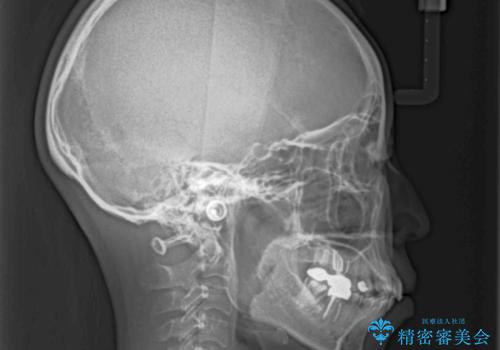

ワイヤー装置の抜歯矯正で横顔の口元の印象をすっきりと

- 口元の閉じにくさを気にして来院された患者様です。

上下ともに歯列が前方に突出していたため、上下左右の第一小臼歯4本を抜去し、ワイヤー装置による矯正治療を行うこととしました。

舌の突出癖による影響もあったため、舌のトレーニングを並行して実施しました。

4本の歯を抜歯したことで、飛び出していた口元が引っ込み、横顔が大きく改善されました。